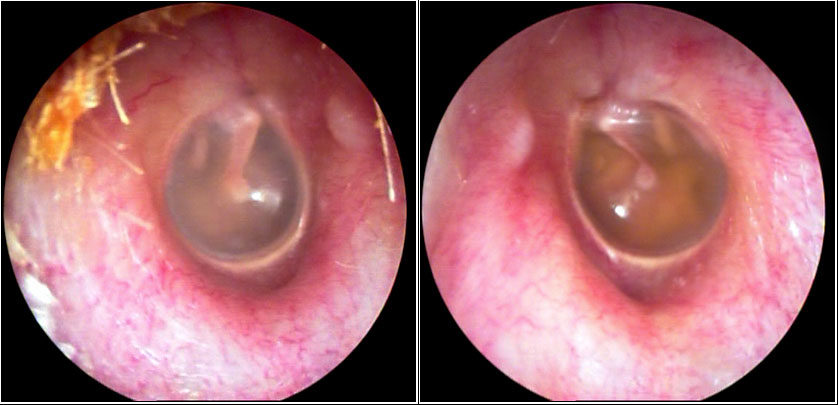

JFC Otitis media supurativa crónica. Colesteatoma.

JFC Otitis media crónica colesteatomatosa.